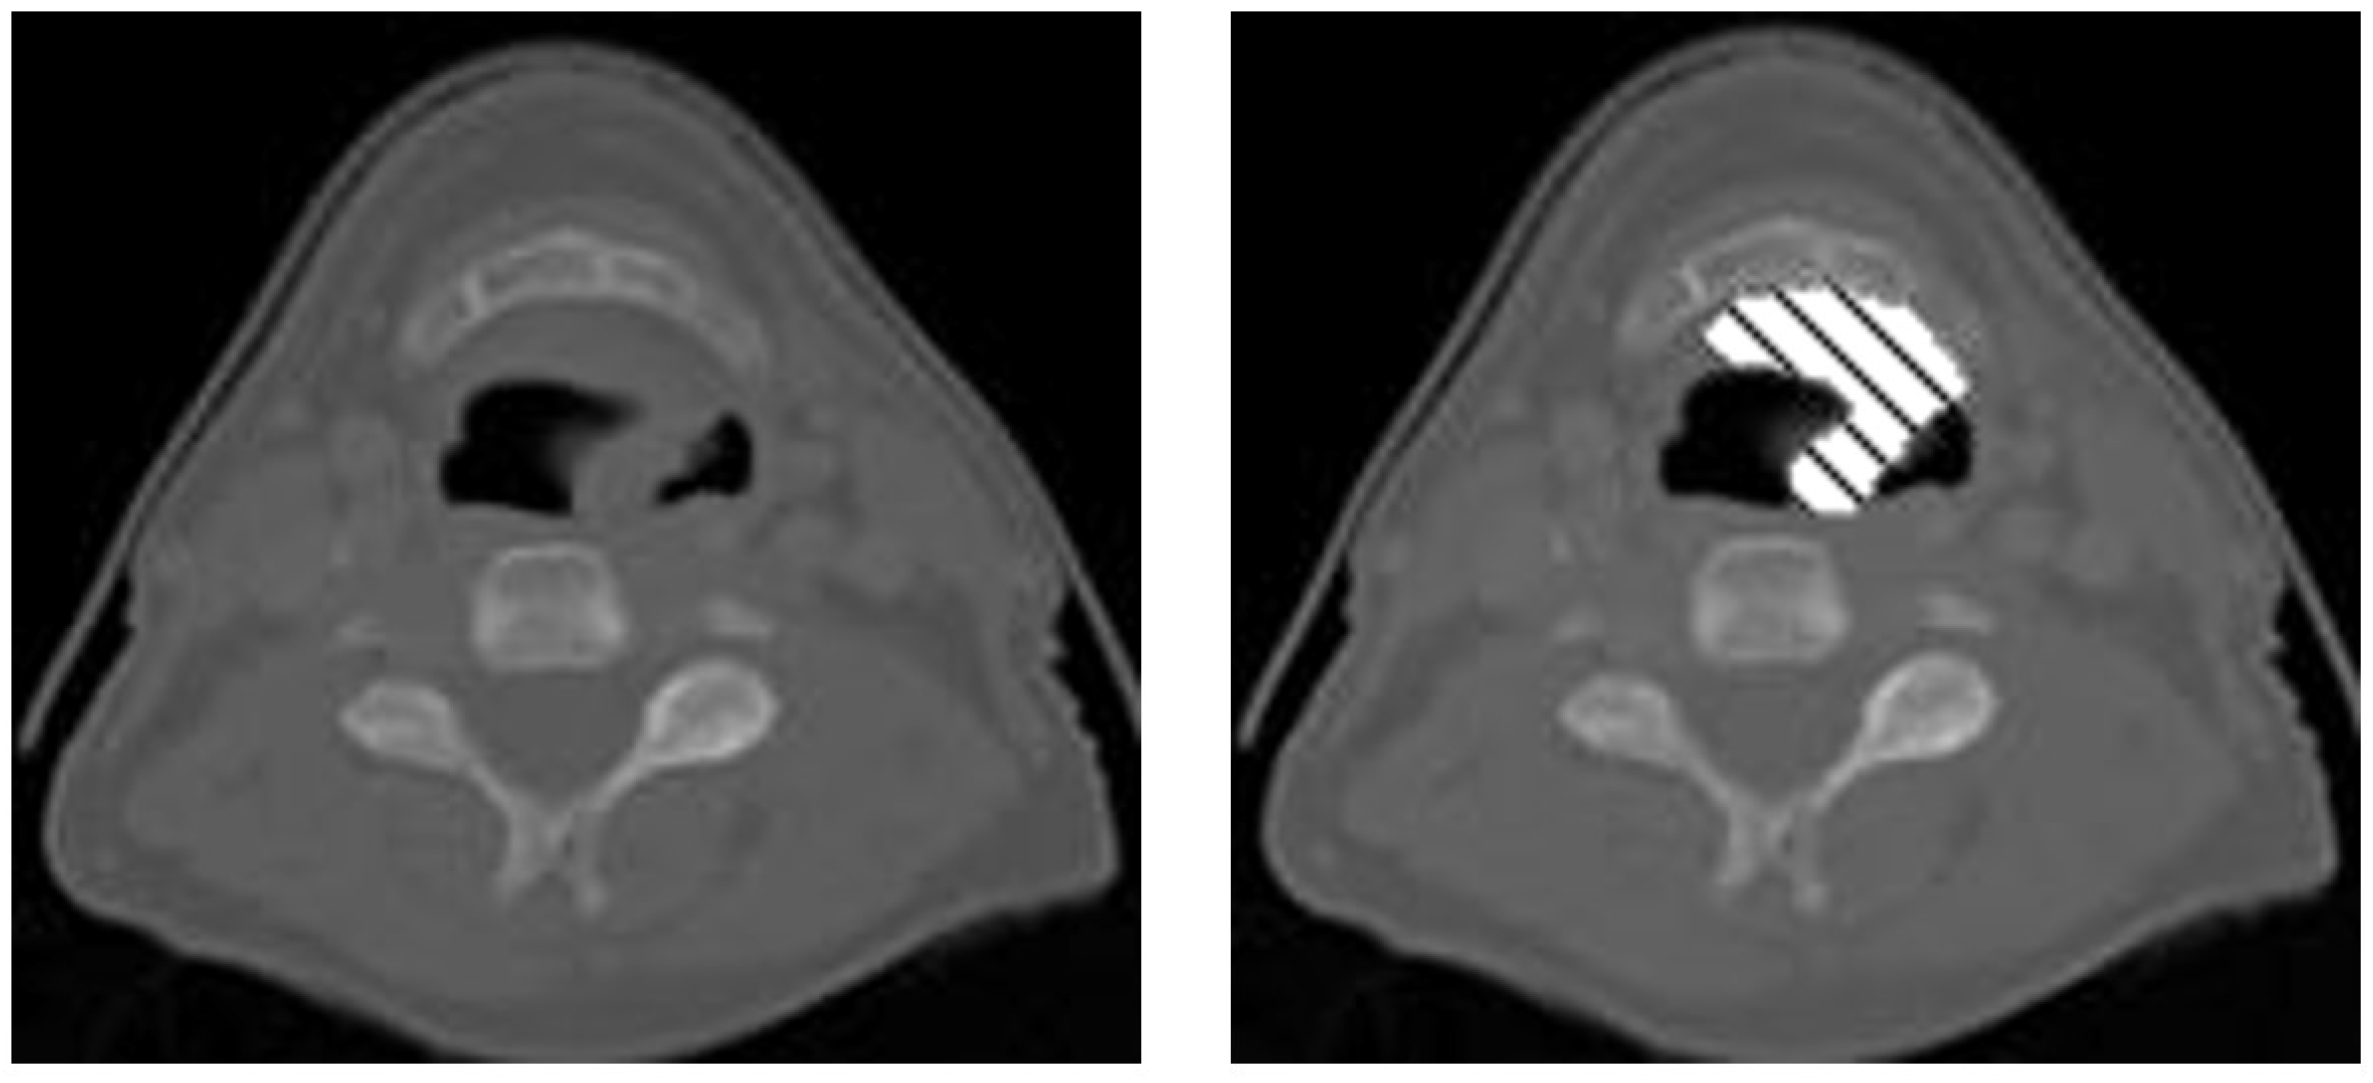

Figure 1.

A CT slice of a patient’s head. The gray-scale portion is the CT image, and the cross-hatched pattern is the contour an oncologist drew on top of the CT scan to plan where radiation should be directed during treatment.

Figure 4 shows the displacement in the GTV when considering a window at the same position in the axial center of the GTV compared with an edge slice. In Figure 4, the center of the GTV has shifted 10 pixels to the right and 4 pixels down from the center to the edge. When calculating the displacement in the GTV from slice to slice across the z-axis, the GTV shifts on average 1.5 pixels on the x-axis and 1.53 pixels on the y-axis. While larger kernel sizes may be able to capture both centers across two or more slices, they will never be appropriately aligned, which could lead to erroneous results the farther we get from the center of the GTV. Pre-existing methods that take advantage of inter-slice connectivity, such as 3D CNNs or CRNNs, convolve or push information forward uniformly across the same pixel locations, even if those pixels are inadequately aligned.

Figure 4.

Displacement between center and edge slice of GTV.